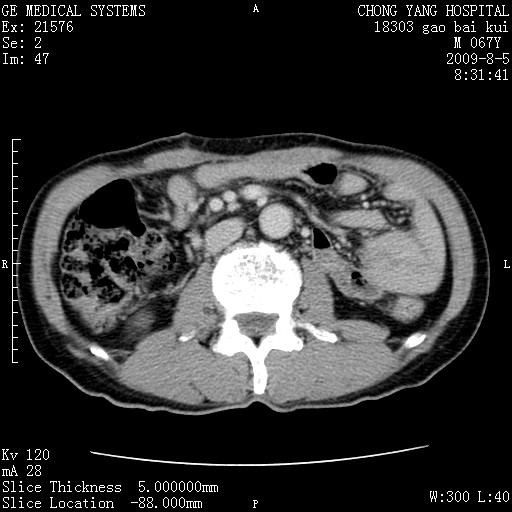

这个也过了,考虑胰腺钩突癌或壶腹癌,不除外胰管粘液乳头瘤伴胰管扩张,肝内胆管积气.

1)考虑胰头癌或壶腹癌并胰管扩张。2)肝外胆管扩张、积气,胆囊影未见;考虑术后改变。3)胃壁增厚?建议必要时行胃镜检查。

虑胰腺钩突癌或壶腹癌,不除外胰管粘液乳头瘤伴胰管扩张,肝内胆管积气.

考虑胰头癌并十二指肠受侵。